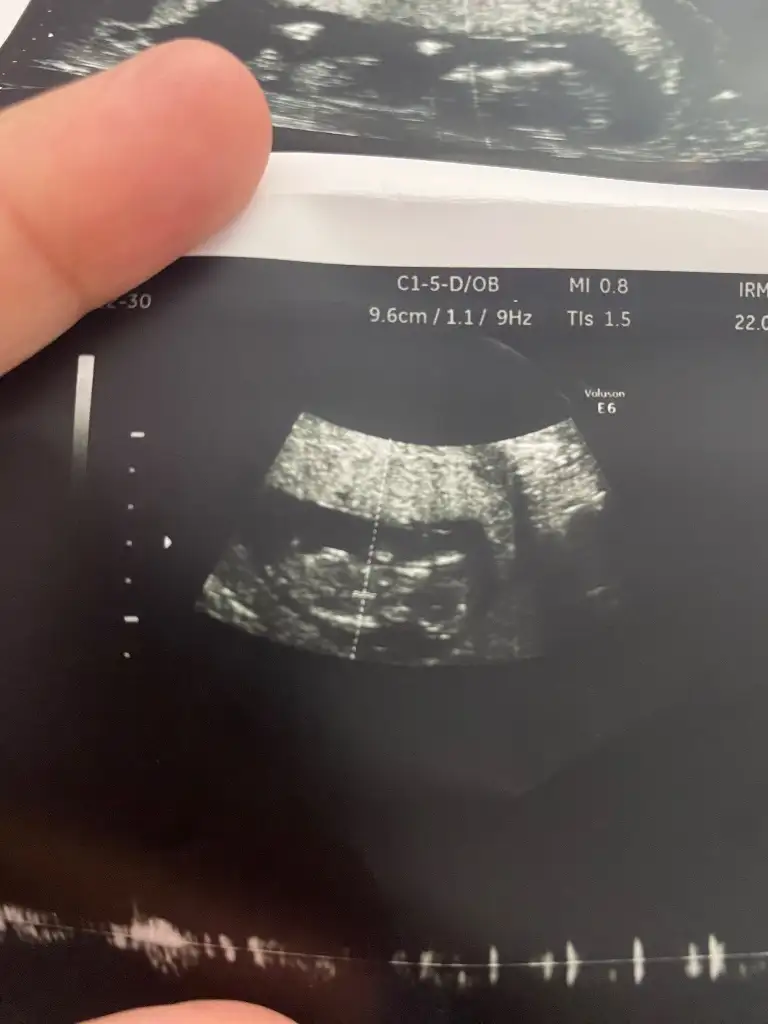

Bunada bakar mısınızKese yuvarlak kız gibi

Başka foto var mı iki bacak arası gibi bu ama bulanık çıkmış gördüğüm çıkıntıysa erkek ama emin olamadımBunada bakar mısınız

Bunlar var canimBaşka foto var mı iki bacak arası gibi bu ama bulanık çıkmış gördüğüm çıkıntıysa erkek ama emin olamadım

Bunada bakar mısınız 11

KızBunada bakar mısınız 11

Başka foto var mı iki bacak arası gibi bu ama bulanık çıkmış gördüğüm çıkıntıysa erkek ama emin olamadım

Ama kalp atış hızı erkeki gösteriyor keseyi tam çözemedim şekli beli olmamış fasulye olursa erkek yuvarlak olursü kız olur genelde

Canım buda kese tam yuvarlak değil gibi erkek hissettim kaç haftalıksın küçük gibi iki hafta geçse sanki daha iyi tahmin yapılıır sendedeEki Görüntüle 3551356 Eki Görüntüle 3551357 benimkinede bakabilir misin canım